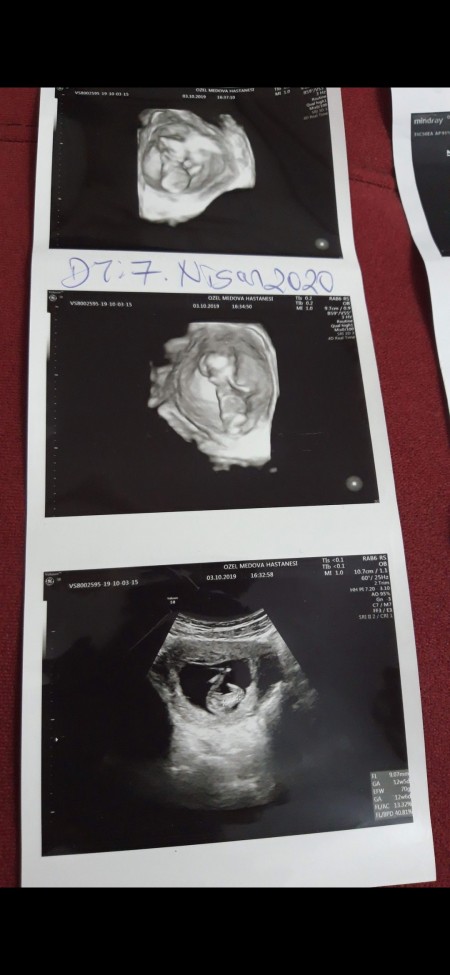

Renkli ultrasonda cinsiyet yanılması olur mu. Ultrasonda ci̇nsi̇yet beli̇rleme hamilelikte gebelikte bebeğin cinsiyeti ultrason ile çok yüksek oranda tespit edilebilmektedir. Ultrasonda cinsiyet yanılması olasılığı her zaman vardır. Ultrason fotoğrafından cinsiyet tahmini ultrasonda cinsiyet yanılması olur mu. Gebelik haberi alındıktan sonra en sık merak edilen şey bebeğin cinsiyeti olur.

Gebeliğin ilk üç ayından itibaren gerekli olur ise bebeğin gelişimi anne bebek arasındaki damarsal iletişimin durumu çoğul gebeliklerde fetusların kan akımlarının etkileşimlerini ölçmek amacıyla renkli doppler inceleme gebeliğin her haftasında yapılabilir. Alttaki videoda 1 22 saniyede ultrasonda bebeğin cinsiyetinin erkek olduğu tespit edilmektedir. Bebeğin cinsiyeti nasıl anlaşılır. Ayrıntılı ultrason sadece cinsiyet taraması yapmak için kullanılmaz.

Haftada artık bebeğin cinsiyeti net bir şekilde görülebilecektir. Ancak 16 haftadan sonra bebeğin duruşu uygun olmadığı için muayenede görülemeyebilir. Renkli doppler ve biyofizik profil i̇nceleme. Haftalarda ultrasonla cinsiyetin görülebilmesi daha uygun olacaktır.